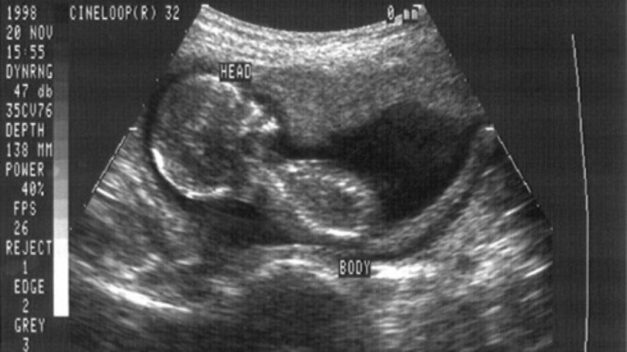

Proof that Indiana’s Ultrasound Law is an Effective Way to Save Unborn Lives

States do not have to sit on the sidelines while abortionists ply their trade by lying to women that the...